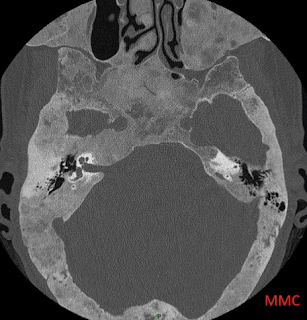

cas n°1

1- Syndrome de McCune Albright